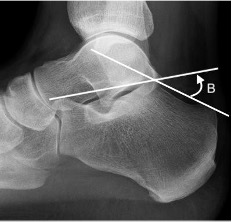

Bohler’s and Gissane's angles

B = Bohler’s angle

Between a line from highest point of calcaneal anterior process to highest point of posterior facet and a line tangential to the posterior superior margin of the calcaneus.

Normal: 20-40°